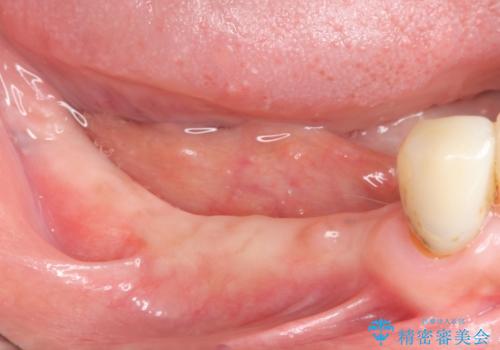

- 奥歯を失い噛めない、しっかりと噛めるようになりたいと希望され来院されました。

奥歯を多数失った場合

入れ歯やインプラントによる咬合機能回復が方法として挙げられますが、両者の咀嚼能力には大きな差があります。